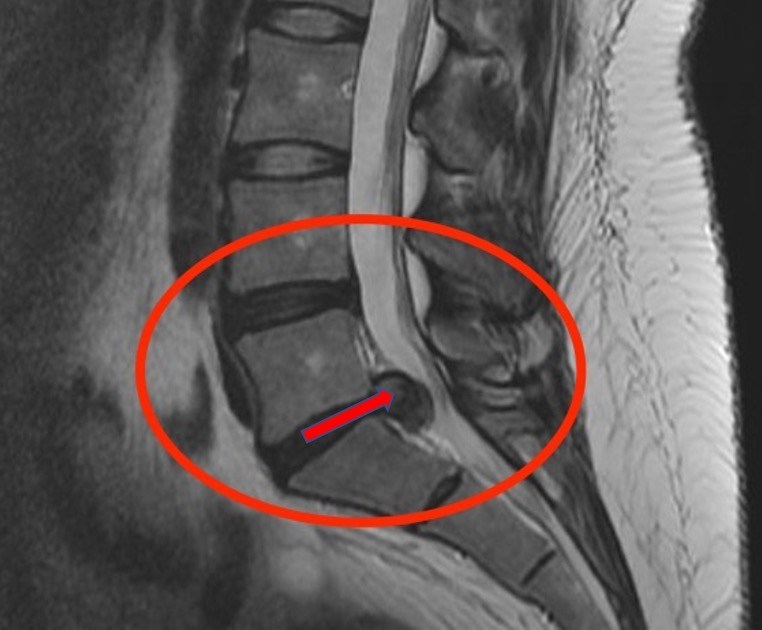

Hérnia de Disco

Compressão Medular

A dor ciática é um sintoma, não uma doença em si. Ela ocorre quando há compressão ou inflamação do nervo ciático, o mais longo do corpo humano, que se estende da lombar até os pés. Essa compressão pode ser causada por hérnia de disco, estenose do canal vertebral, espondilolistese ou até tumores.